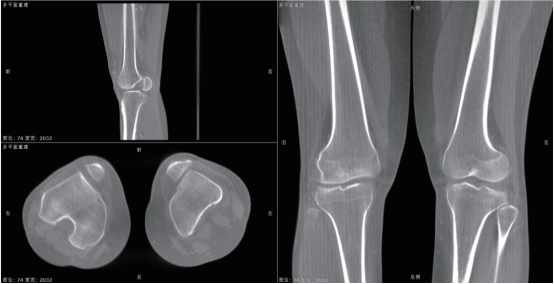

该系统核心优势在于整合动态透视与三维成像技术。在脊柱全长摄影、双下肢负重位检查中,可一次性获取颈椎至骶尾椎的高清全景影像,避免传统分段拍摄的拼接误差,为脊柱侧弯、关节畸形等疾病的力线测量和手术规划提供精准数据。其动态功能成像模块能实时捕捉关节运动状态下的解剖结构变化,清晰显示膝关节屈伸、肩关节活动时的软组织动态,显著提高韧带损伤、关节不稳等隐匿性病变的检出率。